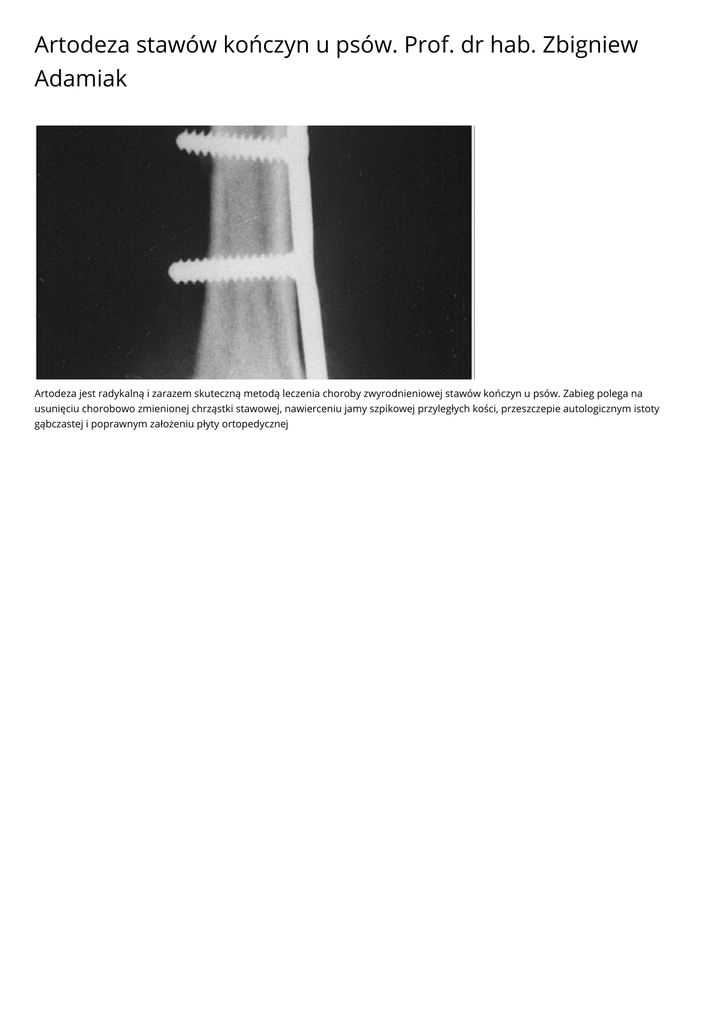

Artodeza jest radykalną i zarazem skuteczną metodą leczenia choroby zwyrodnieniowej stawów kończyn u psów. Zabieg polega na

usunięciu chorobowo zmienionej chrząstki stawowej, nawierceniu jamy szpikowej przyległych kości, przeszczepie autologicznym istoty

gąbczastej i poprawnym założeniu płyty ortopedycznej